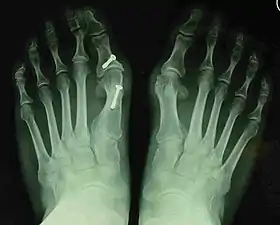

- For severe bunion deformity correction (Fig. 7)

- For recurrence correction after osteotomy procedure (Fig. 8)

Late deformity recurrence can happen after osteotomy (bone-breaking) procedures because osteotomy surgeries do not specifically stabilize first metatarsal bone.

For recurrence correction after fusion procedure (Fig. 9) Metatarsus primus varus deformity and pain recurred 6 months after modified Lapidus procedure and it could also be again corrected by the syndesmosis procedure.